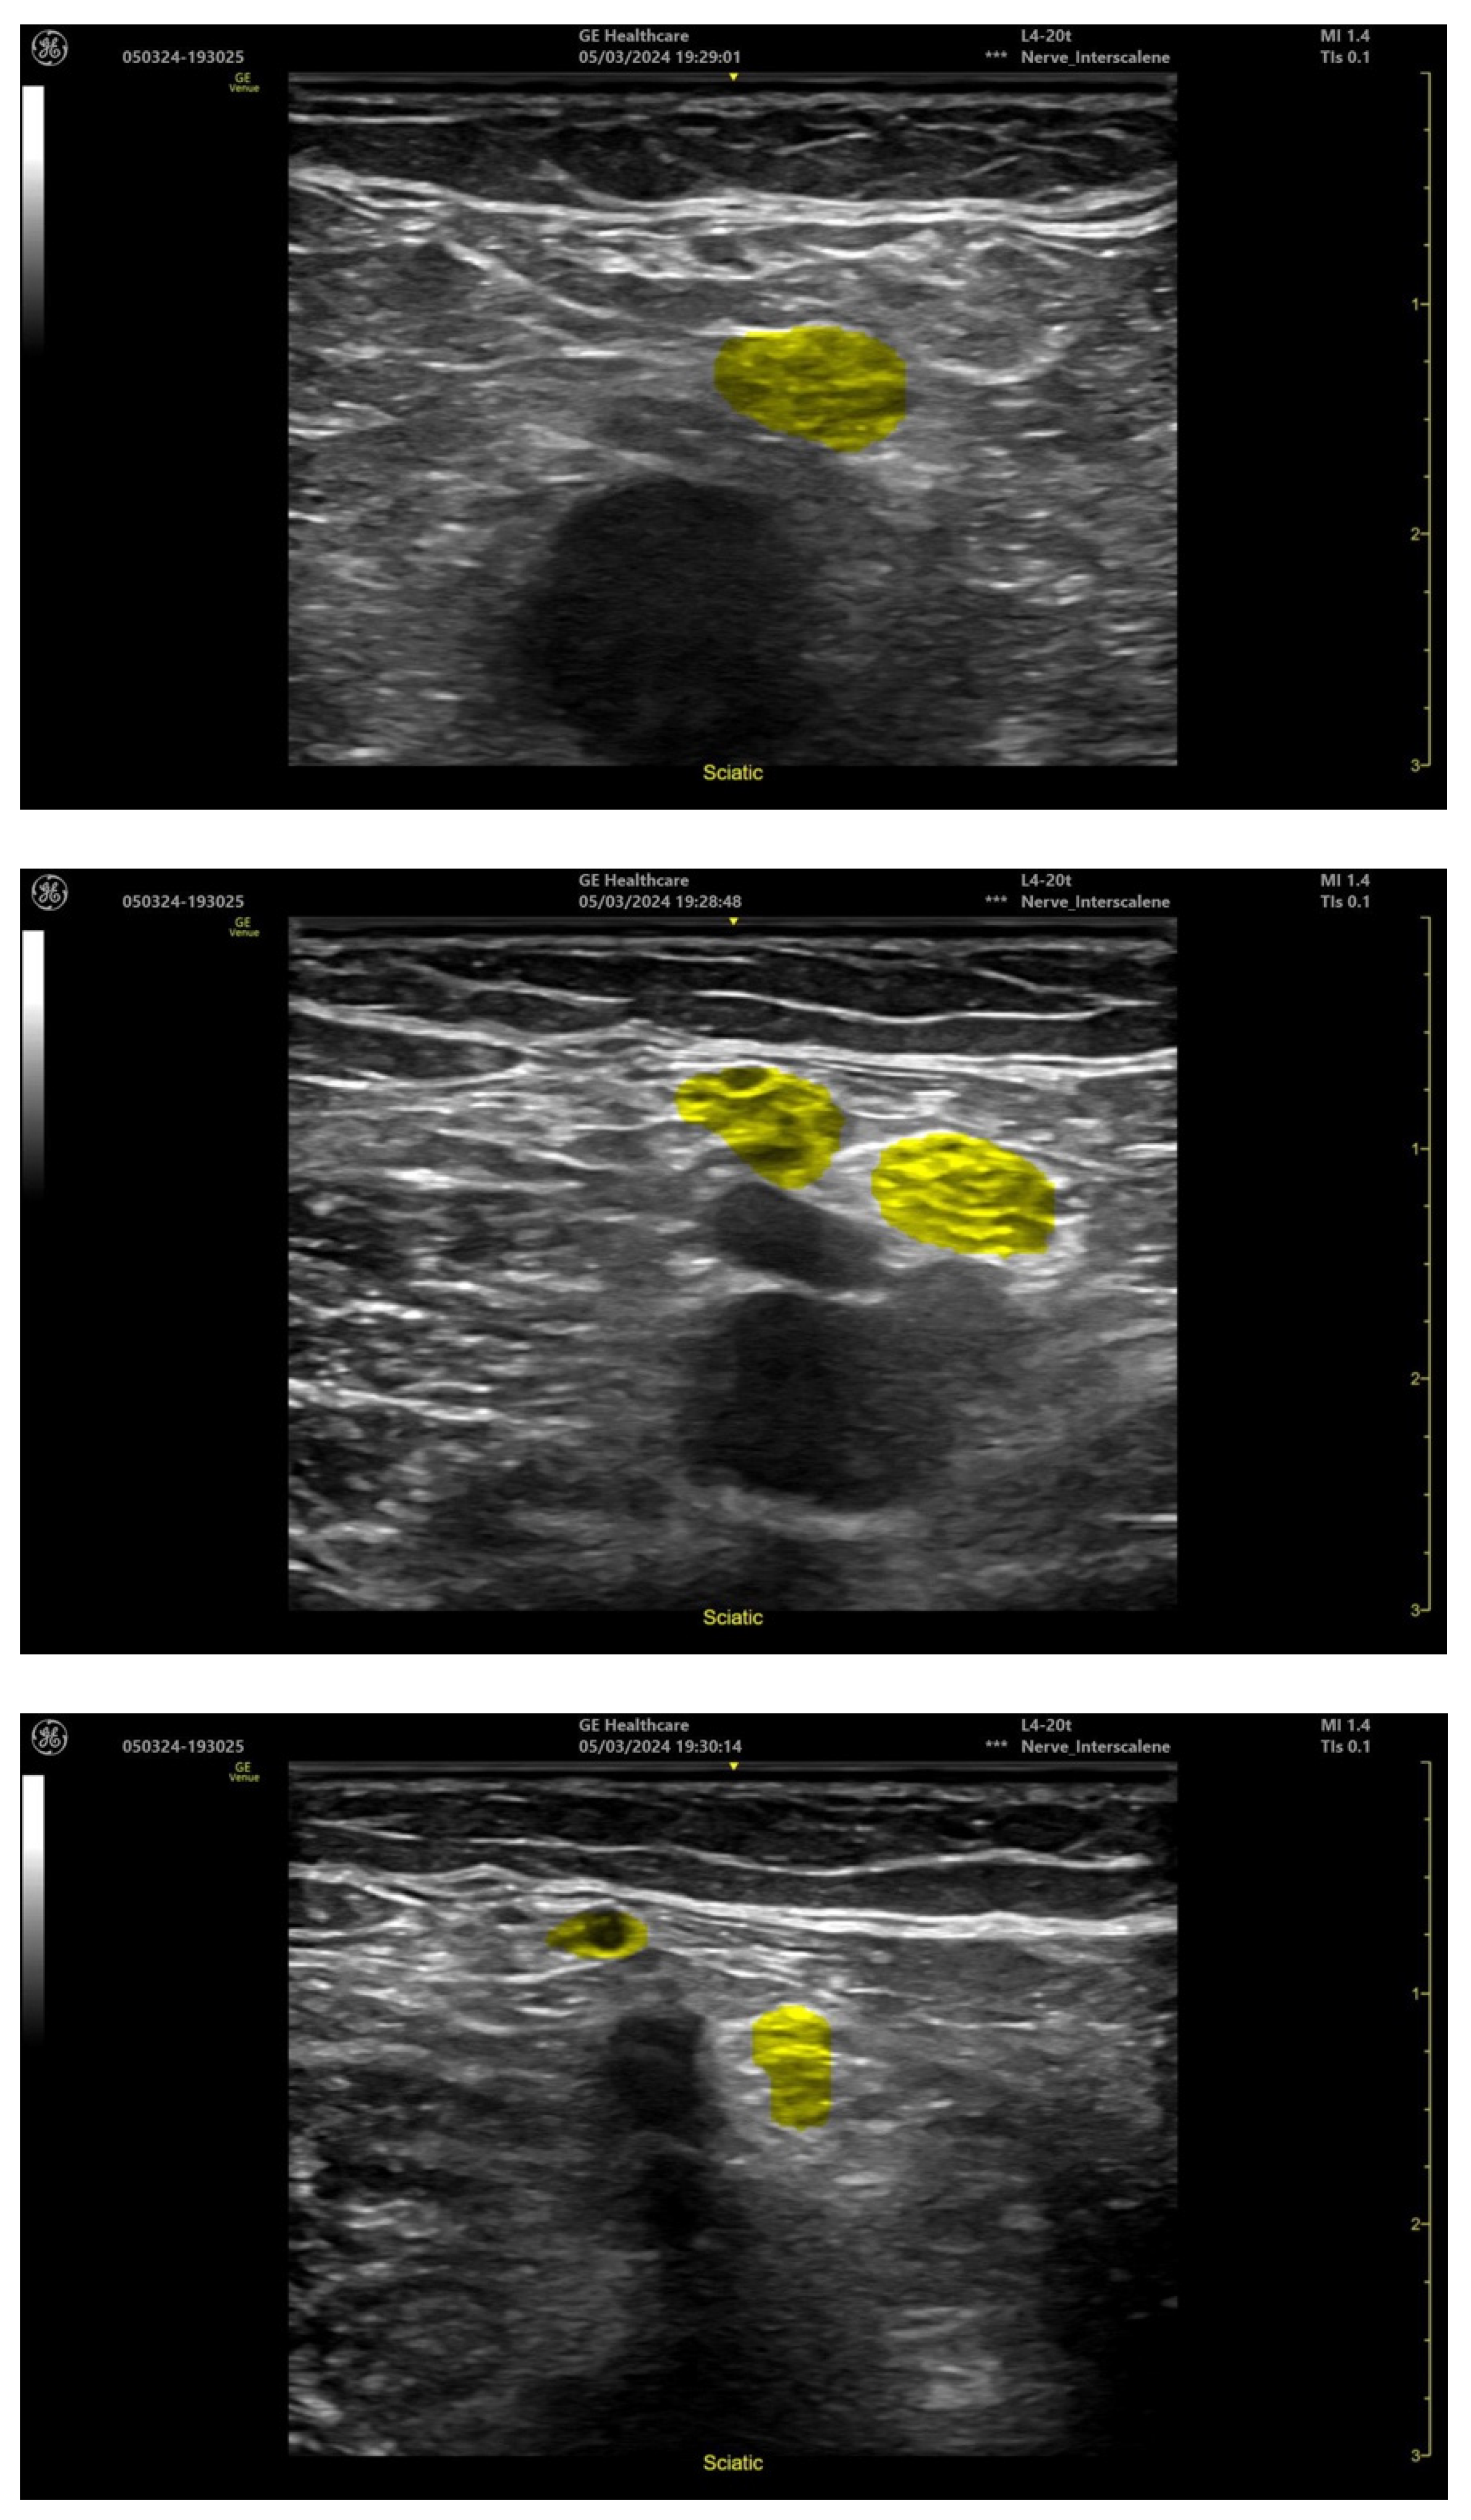

- Popliteal-level sciatic nerve;

| Popliteal Level Sciatic Nerve | ||

| Popliteal artery | 39/40 (97.5%) | 1/40 (2.5%) |

| Sciatic nerve | 40/40 (100%) | 0/40 (0%) |

| Tibial nerve | 39/39 (100%) | 0/39(0%) |